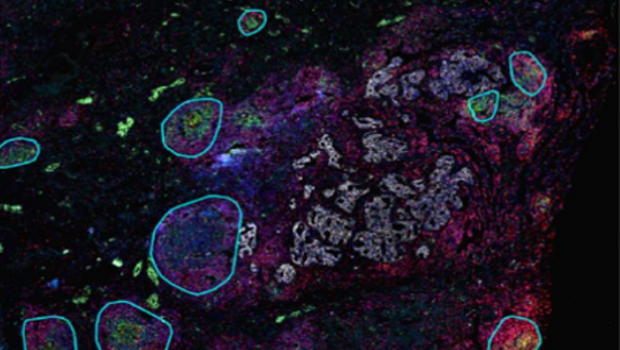

通过识别组织图像中标志物的染色信息,自动调节荧光强度并识别出图像中 TLS 结构进行标注,进一步定量分析可得到图像中每个 TLS 独立的定量数据,同时可进一步对三级淋巴结构的内部进行空间分析。